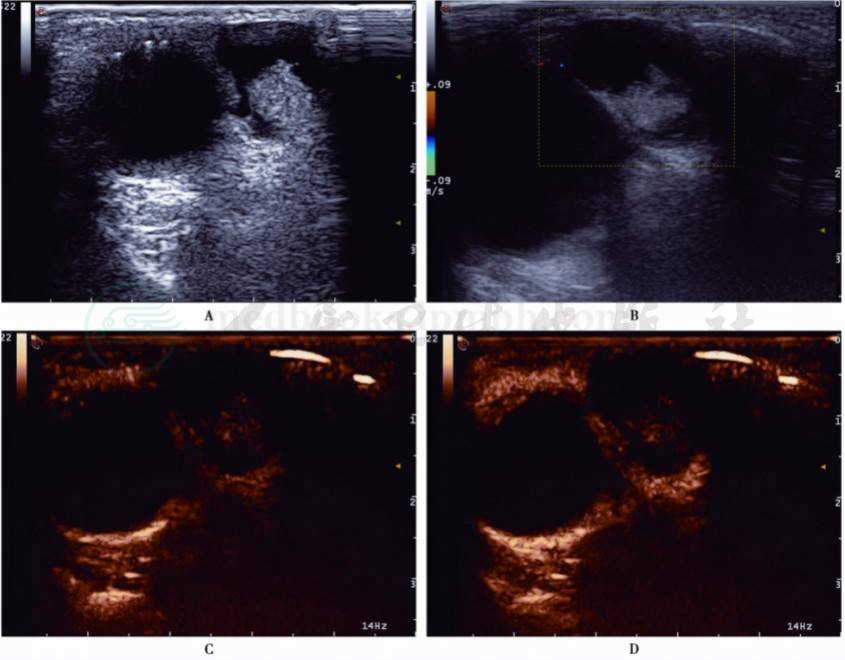

图2 女,45岁,左眼眶外侧表皮囊肿

A、B﹒左眼眶外侧囊实混合性肿块,无血流信号;C、D﹒注入造影剂后肿块无增强